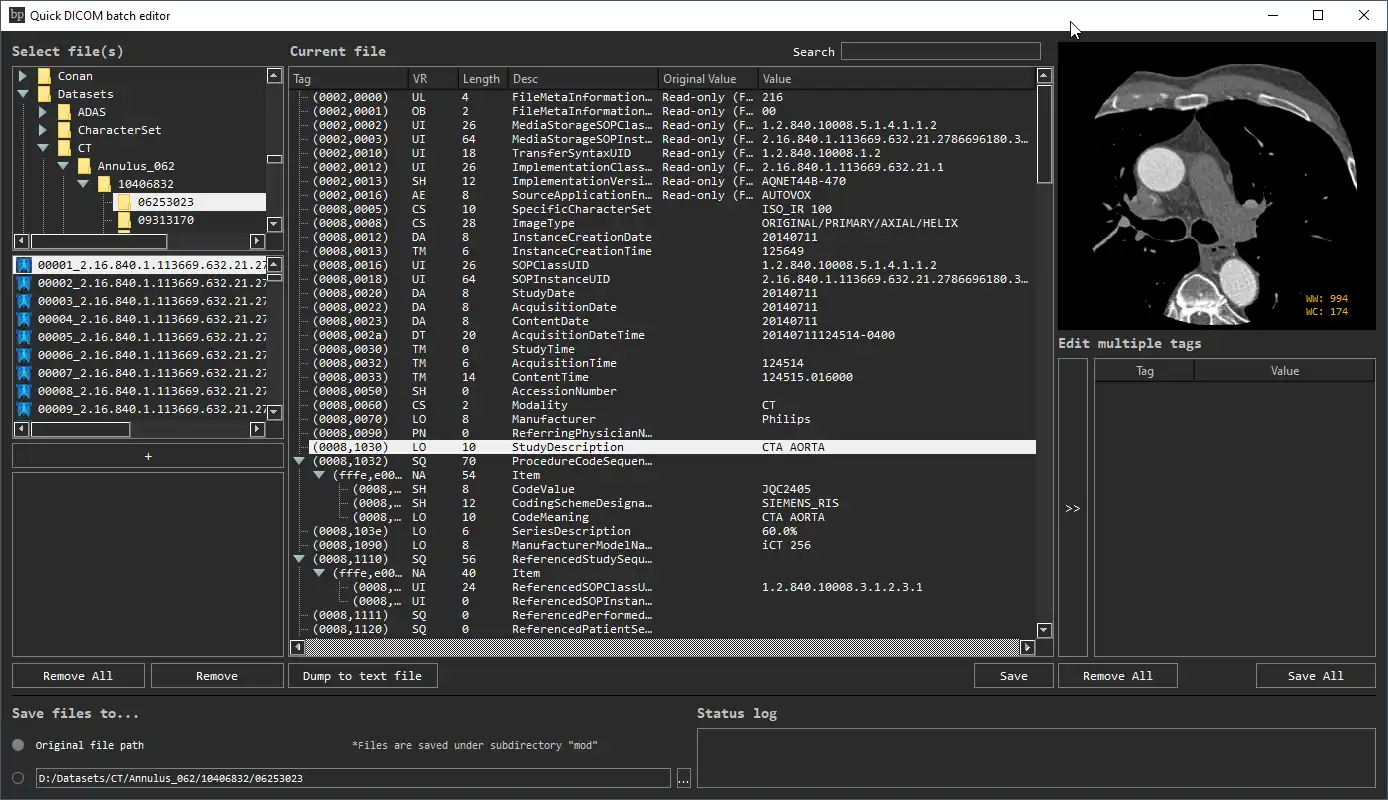

SCREENSHOTS

* Descrição geral

- Ver e modificar tags DICOM de um único arquivo

- Visualize e modifique as tags DICOM de vários arquivos

- Despeje as tags DICOM em um arquivo de texto

- Imagens de visualização (dados de pixel DICOM)

- Visualize e modifique as tags DICOM de um único arquivo

- Visualize e modifique as tags DICOM de vários arquivos

- Despejar tags DICOM em um arquivo de texto

- Imagens de visualização (dados de pixel DICOM)